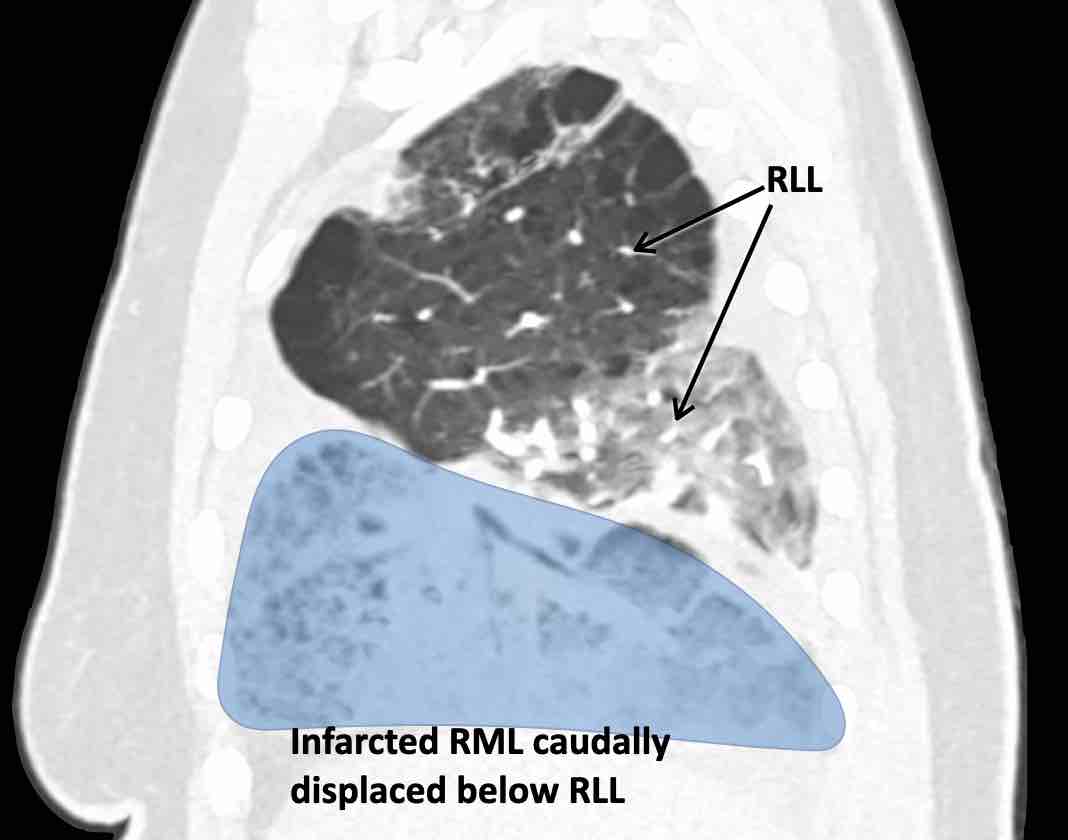

Các hình ảnh này của một bệnh nhân nữ 65 tuổi sau khi đã cắt thùy trên phổi phải trước đó.

Theo dõi lần lượt các phế quản giúp xác định mỏm cắt thùy trên phổi phải (RUL), phế quản thùy giữa bị tắc nghẽn và các phế quản thùy dưới còn thông.

Điều này xác định mô phổi bị di lệch xuống dưới chính là thùy giữa phổi phải (RML), thấy rõ nhất trên mặt phẳng đứng dọc.

Thùy giữa phổi phải bị phù nề và không còn được tưới máu.

Ngoài ra còn thấy hình ảnh ứ máu và xẹp phổi ở các phân thùy đáy của thùy dưới phổi phải (RLL), hiện nằm phía trên thùy giữa phổi phải đã bị nhồi máu.